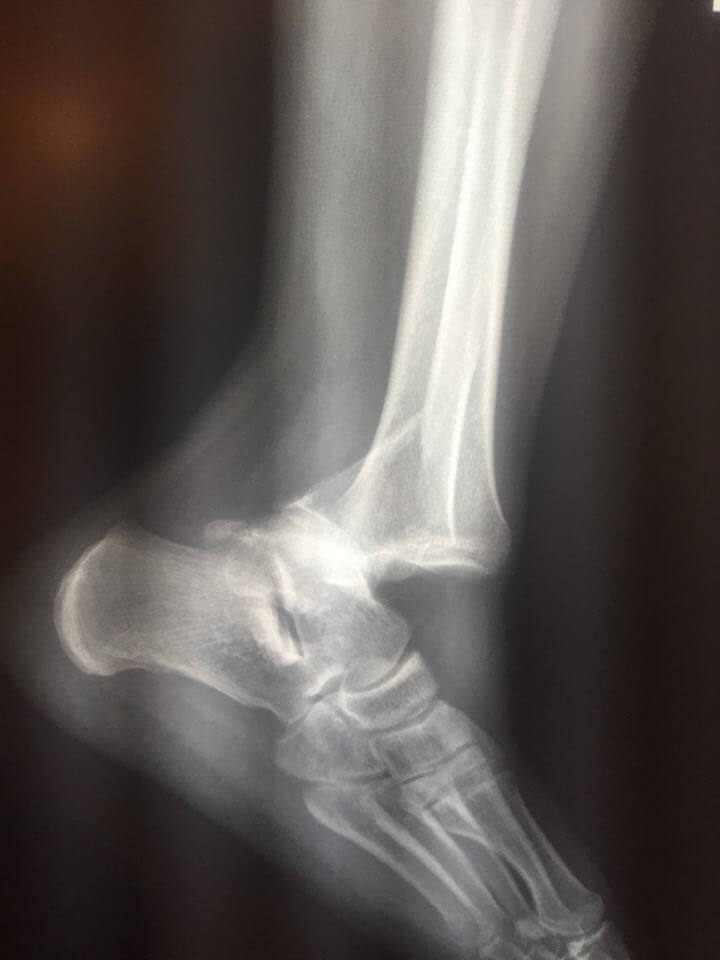

Mike has since had surgery and gotten some great new hardware for his ankle, which was broken in several spots – I’ll throw some X-Rays up if Mike is cool with it. He should be on a walking cast by August and we’re thinking of a late season paddle in October perhaps.